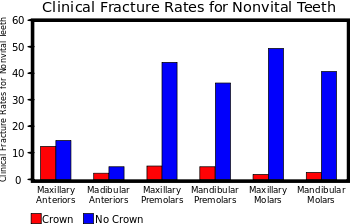

When teeth undergo endodontic treatment, or root canal therapy, they are devitalized when the nerve and blood supply are cut off and the space which they previously filled, known as the "pulp chamber" and "root canal", are thoroughly cleansed and filled with various materials to prevent future invasion by bacteria. Although there may very well be enough tooth structure remaining after root canal therapy is provided for a particular tooth to restore the tooth with an intracoronal restoration, this is not suggested in most teeth. The vitality of a tooth is remarkable in its ability to provide the tooth with the strength and durability it needs to function in mastication. The living tooth structure is surprisingly resilient and can sustain considerable abuse without fracturing. But after root canal therapy is performed, a tooth becomes extremely brittle and is significantly weaker than its vital neighbors.

The average person can exert 150–200 lbs (70–90 kg) of muscular force on his or her posterior teeth, which is approximately nine times the amount of force that can be exerted in the anterior. If the effective posterior contact area on a restoration is 0.1 mm², over 1 million PSI of stress is placed on the restoration. Therefore, posterior teeth (i.e. molars and premolars) should in almost all situations be crowned after undergoing root canal therapy to provide for proper protection against fracture (mandibular premolars, being very similar in crown morphology to canines, may in some cases be protected with intracoronal restorations). Should an endodontically treated tooth not be properly protected, there is a chance of it succumbing to breakage from normal functional forces. This fracture may well be difficult to treat, such as a "vertical root fracture". Anterior teeth (i.e. incisors and canines), which are exposed to significantly lower functional forces, may effectively be treated with intracoronal restorations following root canal therapy if there is enough tooth structure remaining after the procedure.